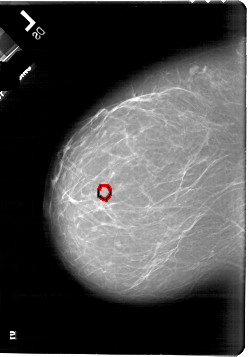

A_1818_1.RIGHT_CC

RIGHT_CC LINES 6226 PIXELS_PER_LINE 4561 BITS_PER_PIXEL 12 RESOLUTION 43.5 NON_OVERLAY

FILE: A_1818_1.LEFT_MLO.OVERLAY

TOTAL_ABNORMALITIES 1

ABNORMALITY 1

LESION_TYPE CALCIFICATION TYPE PLEOMORPHIC DISTRIBUTION CLUSTERED

ASSESSMENT 4

SUBTLETY 1

PATHOLOGY BENIGN

TOTAL_OUTLINES 1

BOUNDARY